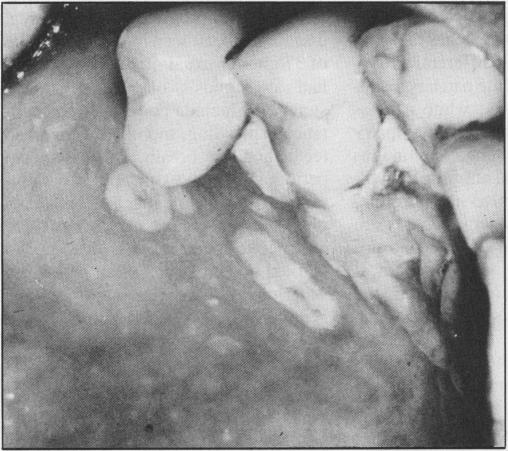

The AIDS epidemic continues. All health-care workers, including physicians and dental personnel, may be instrumental in recognizing risk factors associated with Acquired Immunodeficiency Syndrome (AIDS) and Human Immunodeficiency Virus (HIV) infection. Oral signs and symptoms of HIV infection may be the first presentation of the disease or may develop during the course of the disease and require management. Knowledge of the signs, symptoms and associated infections and tumours is needed to assist in recognition, diagnosis, and treatment.